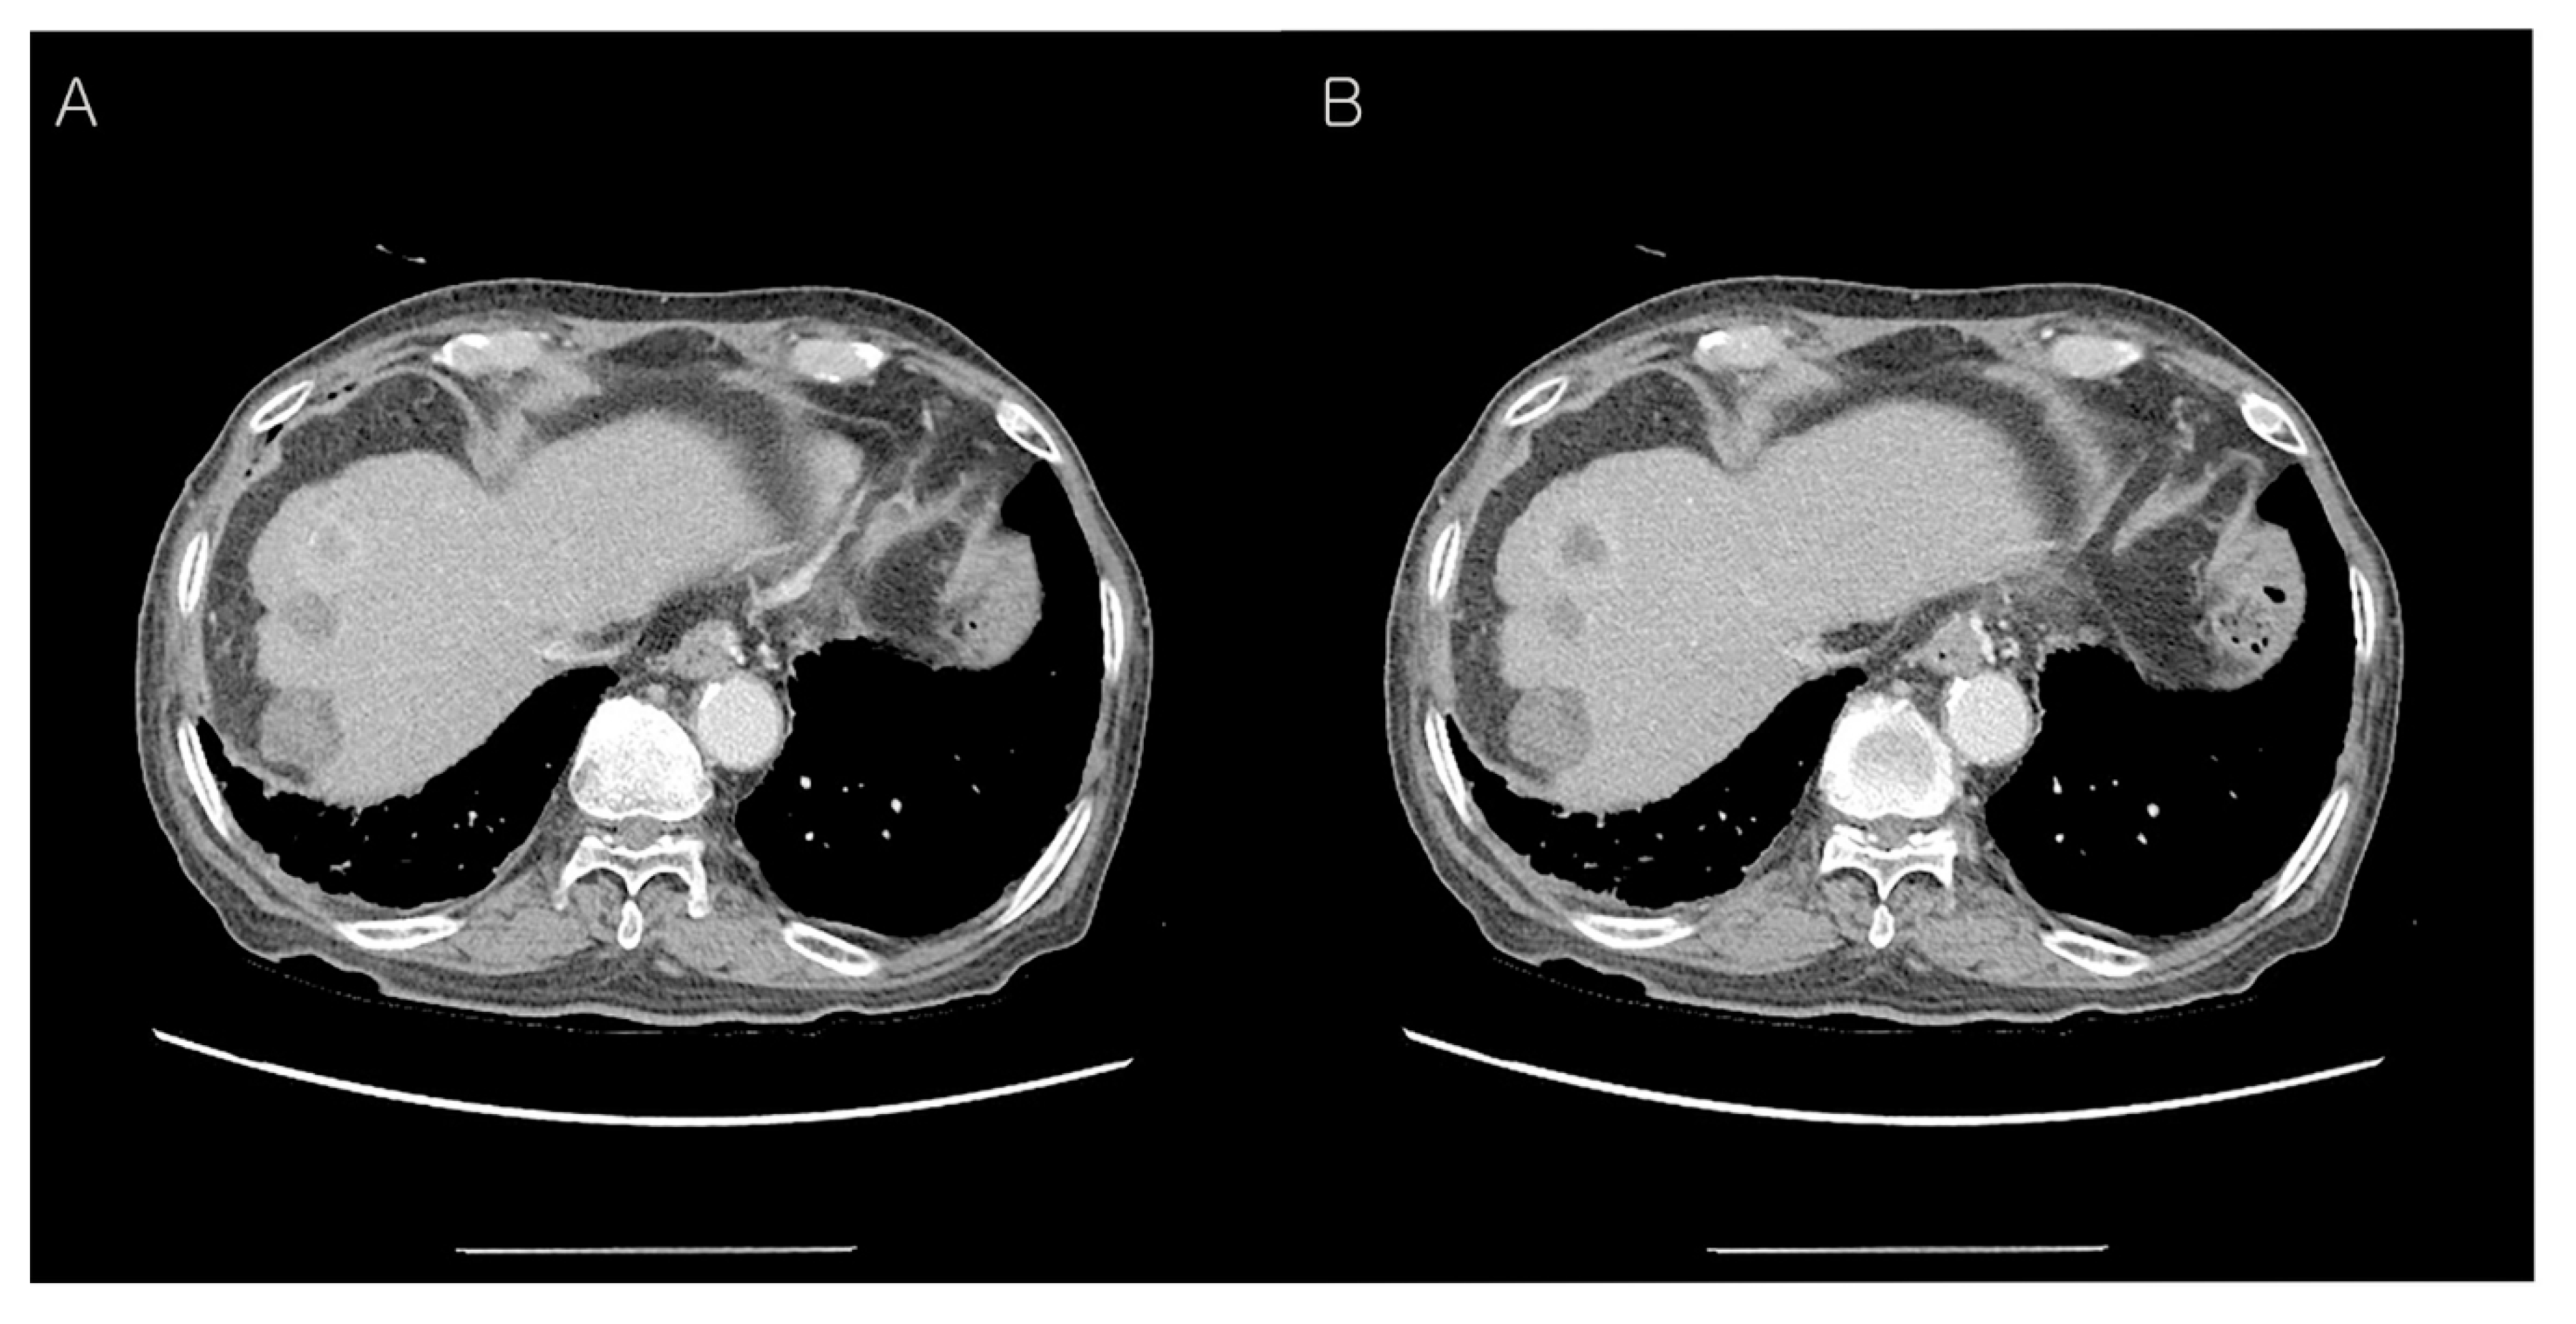

Abdominal CT findings post-operation, 10 months later. Ten months after the operation, the follow-up CT revealed a heterogenous enhancing mass (upper) in segment 8 of the liver with two previous RFA-treated hepatic masses (middle and lower) (A,B). After the third radiofrequency ablation for the new-developed hepatic mass, the patient is still alive.